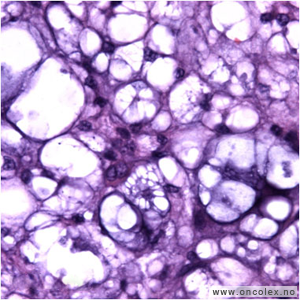

Kondrosarkom er en malign tumor bestående av bruskmatrix og bruskceller. Per definisjon skal en ikke se produksjon av osteoid, men det kan være reaktiv bendannelse.

Kondrosarkom inndeles på basis av lokalisajon (sentral, perifer, juxtakortikal), tilstedeværelse av en preeksisterende lesjon (de novo eller sekundært kondrosarkom utviklet på for eksempel et osteokondrom), celledifferensiering (lav/middels/høygradig malign) og histologiske varianter (klarcellet, mesenkymal, dedifferensiert).

Kondrosarkomer skilles fra enkondromer ved at den viser større cellerikdom og mer pleomorfi. Det ses stor variasjon i cellestørrelse, og ofte tokjernede celler. Mitoser ses sjelden. Myxoide partier og cystiske oppklaringer trekker i malign retning. Forkalkninger og forbening kan ses. Tumor infiltrerer ofte inn i cortex eller ut i omgivende bløtvev. Kondrosakromer av høyere malignitetsgrad kan vise stor atypi og rikelig myxoid matrix. Vekstmønsteret kjennetegnes av at tumor fyller benmargen mellom benbjelkene slik at benbjelkene blir lukket inne i tumorvevet. Bruskvevet ligger da på begge sider av benbjelkene og helt inntil disse (såkalt "permeation"). Immunhistokjemi viser positivt funn for vimentin og protein S-100, men negativt funn for cytokeratin og EMA.

Lysmikroskopibilde av høygradig malignt kondrosarkom. |